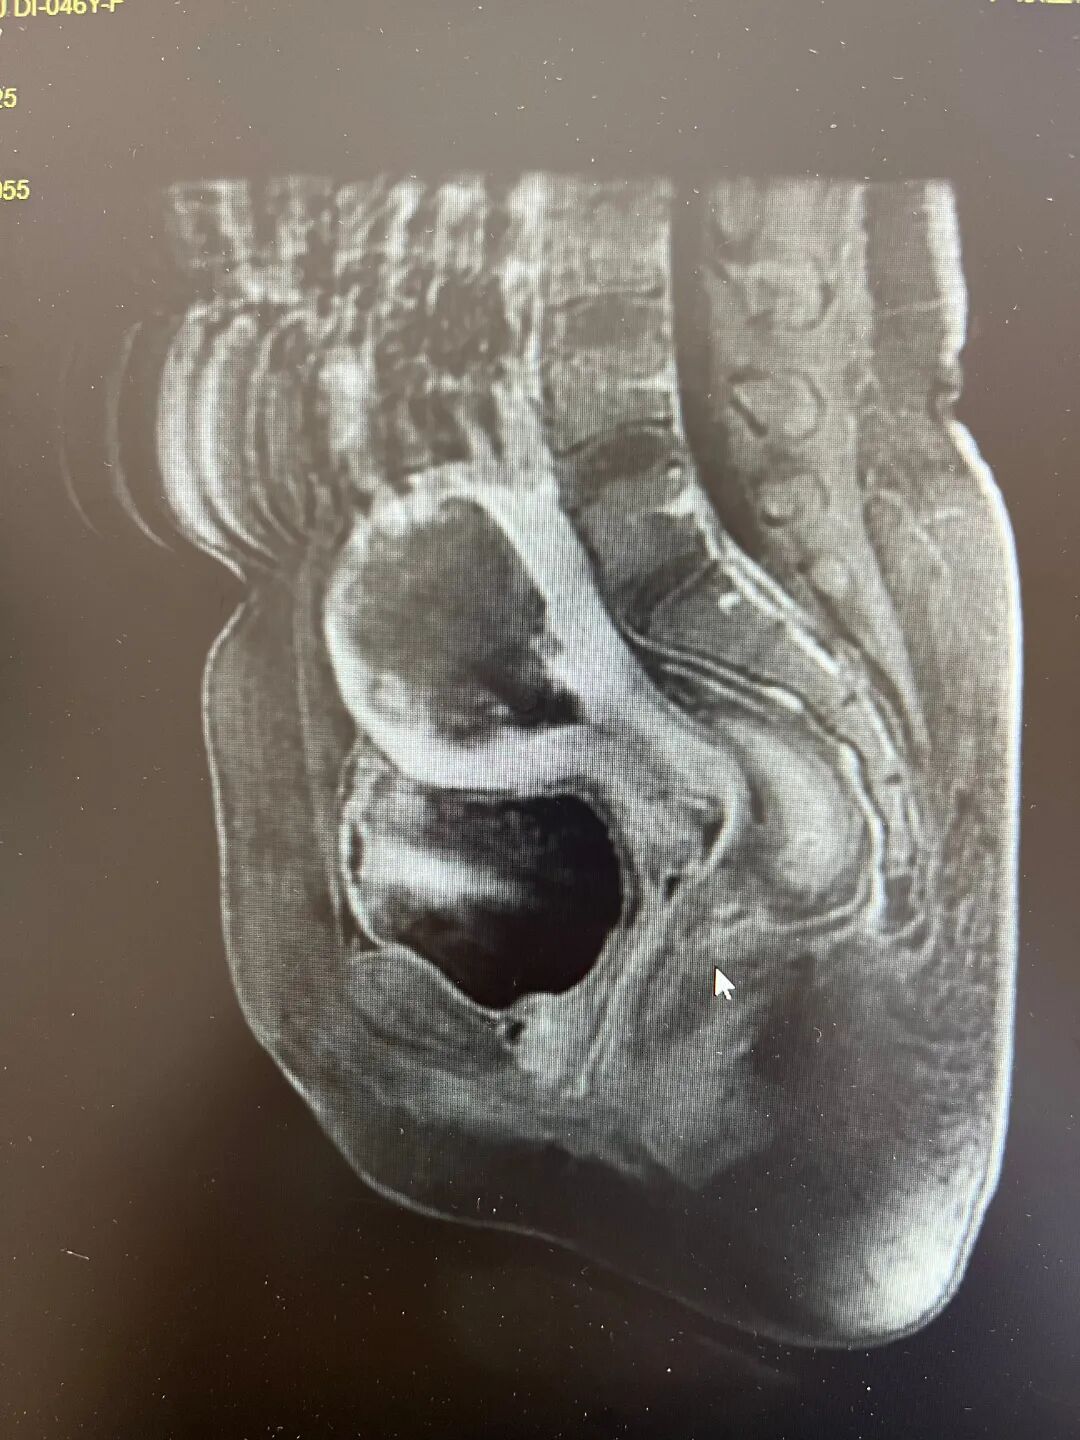

随即,胡媛华副主任医师为梁女士开出了相关的检查,检查发现,梁女士体内的子宫病灶清晰可见,子宫大如怀孕两个月,综合考虑之下,她建议梁女士科选择进行海扶刀治疗,这种方式既能去除子宫内的病灶,也可以保留子宫。

最终,梁女士听从了医生的建议,在我院海扶微无创治疗中心接受了海扶刀治疗,治疗过程仅用了65分钟,全程无创伤也无痛苦。治疗后,梁女士的核磁共振(MRI)检查可见,其体内子宫的病灶清除效果良好。术后经过一晚的观察,无异常即安排顺利出院了。

术前MRI检查结果